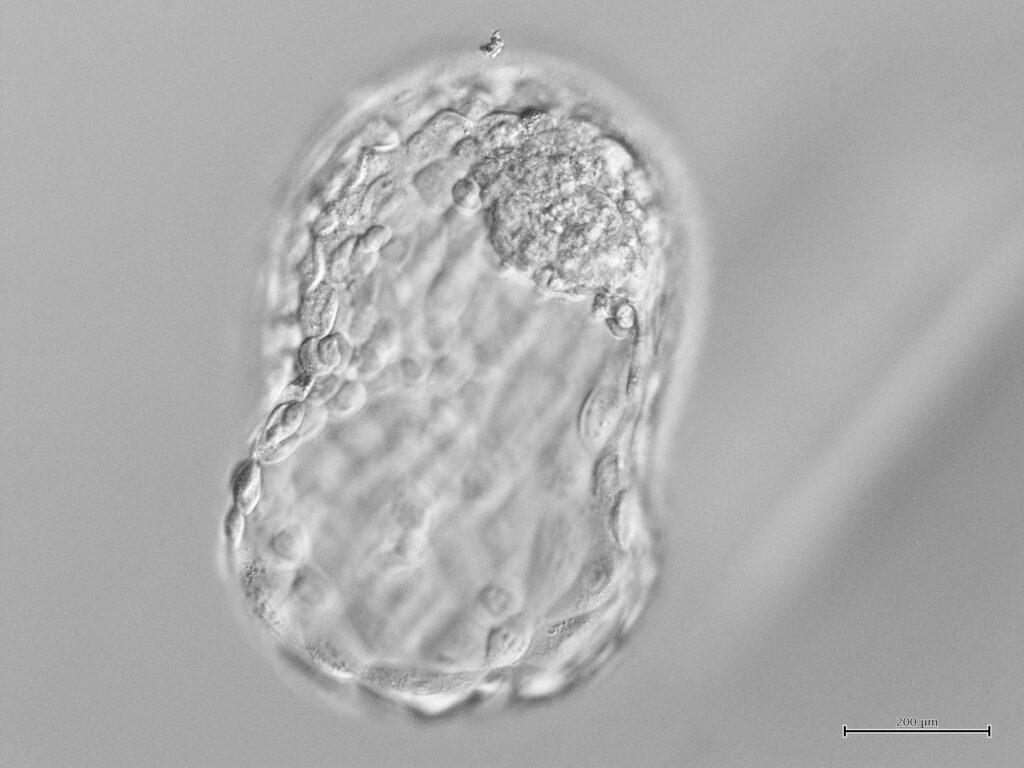

A lo largo de todo el tratamiento, todas las placas y/o tubos de muestras de una misma paciente son identificados con un mismo código, de manera que pueda comprobarse su identidad en cada fase (punción ovárica, fertilización, transferencia embrionaria y congelación).

Las muestras de diferentes pacientes nunca coinciden en la misma zona de trabajo. Cada paciente tiene su posición única asignada en las distintas incubadoras durante todo el proceso, permitiendo así, un seguimiento completamente seguro de todo el tratamiento, ofreciendo una garantía de seguridad extraordinaria.